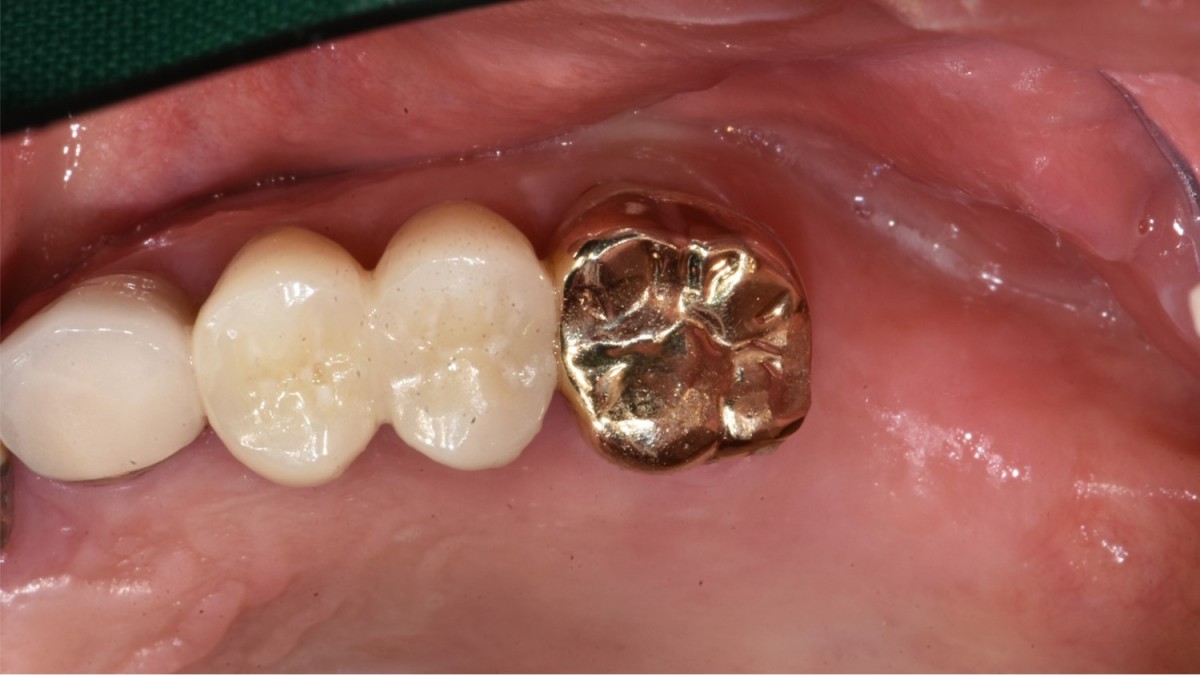

A 57-year-old male patient recently underwent

implant restoration on the maxillary right molar. This time, he is scheduled to

proceed with the left molars. (ARUM implant system)